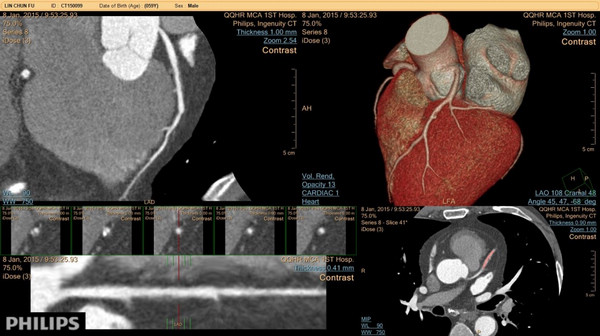

近日,附属一院引进了飞利浦256层极速CT,现已成功开展心脏冠状动脉CTA、头颈部CTA、胸腹部CTA、下肢血管CTA、泌尿系统CTU、门静脉CTV、骨骼三维成像、肺高分辨CT等多种检查项目。该设备为新一代高端CT,与以往CT相比具有旋转速度更快、辐射剂量更低、扫描范围更大、智能程度更高、图像质量更好等特点。

飞利浦256层极速CT检查冠状动脉狭窄成像图